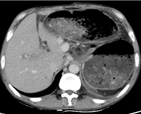

入院CT

临床诊断:肝硬化、门静脉高压 门静脉、脾静脉血栓 脾功能亢进 食管、胃底静脉曲张(重度)门脉高压性胃病